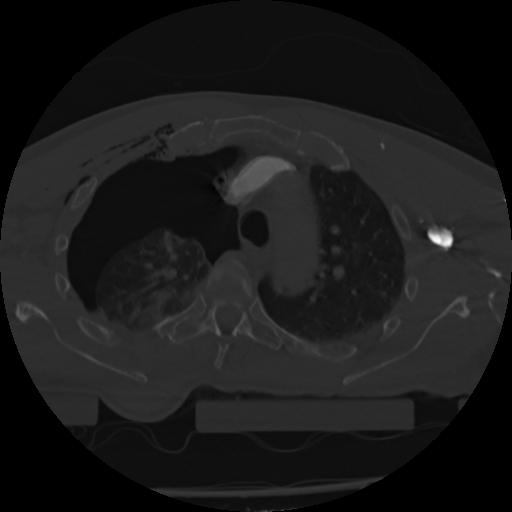

22 ANGIO,CE,Vol,0.5,ANGIO,,